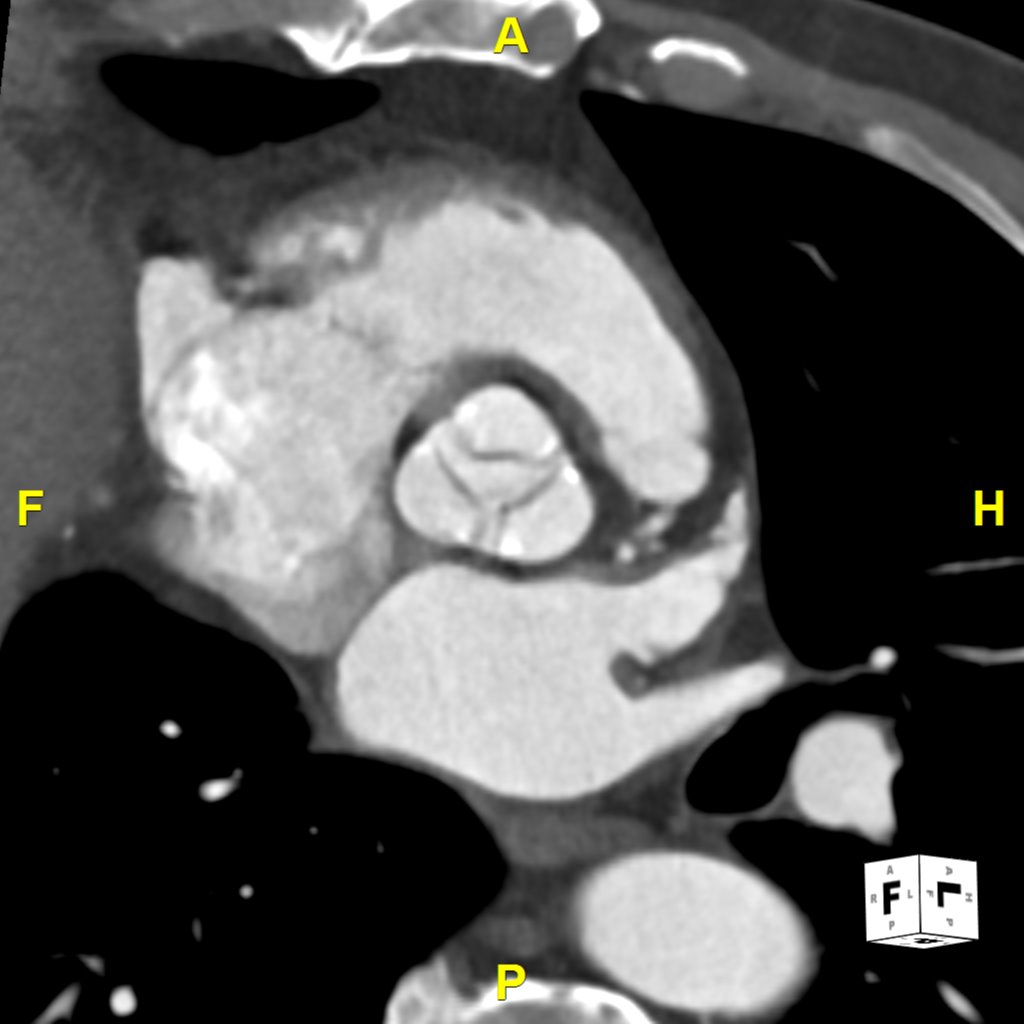

Using 3D imaging in the TAVR planning process allows for the evaluation of aortic root dimensions, annulus size, and the morphology of the aortic valve complex. It provides insights into the spatial relationships between the aortic valve and surrounding coronary arteries, highlighting potential challenges and guiding the selection of the appropriate valve size and optimal implantation approach.

Additionally, CT angiography assesses the iliofemoral arteries, determining their suitability for catheter access by identifying any calcifications, occlusions, or tortuosities that could impact the procedure.